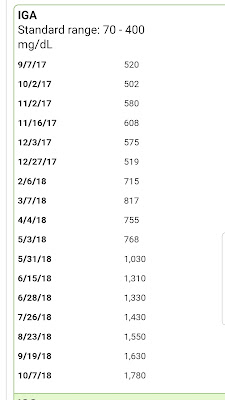

I just can't believe that 9 years ago this time Myeloma was RAGING inside of me, and I didn't know it yet.... My IGA was close to 5800 (normal = 70-400). My M Protein was over 4.3 (normal = 0) and my first Bone Marrow Biopsy showed 70% cancerous myeloma plasma cells! And here I am to talk about it, almost 9 years later, having survived more rounds chemo than I can count, a Stem Cell Transplant, and all the 9 years of side effects I have endured! But I'll reminisce about all of this soon...